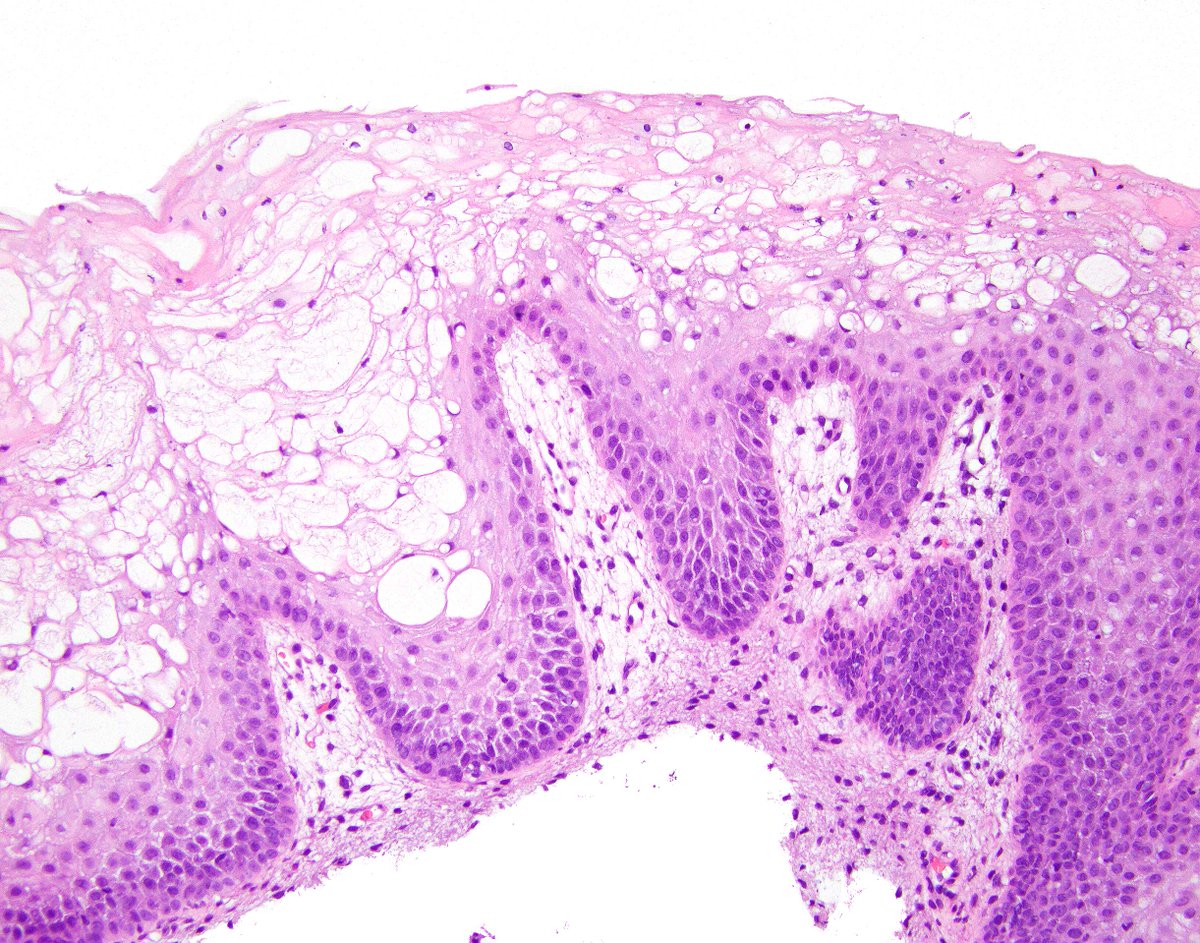

Oxyntic gland adenoma (or chief cell adenoma or gastric adenocarcinoma with chief cell differentiation). A parietal cell is indicated.  The PAS/AB stain shows normal foveolar cells at the surface.  These are associated with a benign outcome following polypectomy. PMID: 22472957.